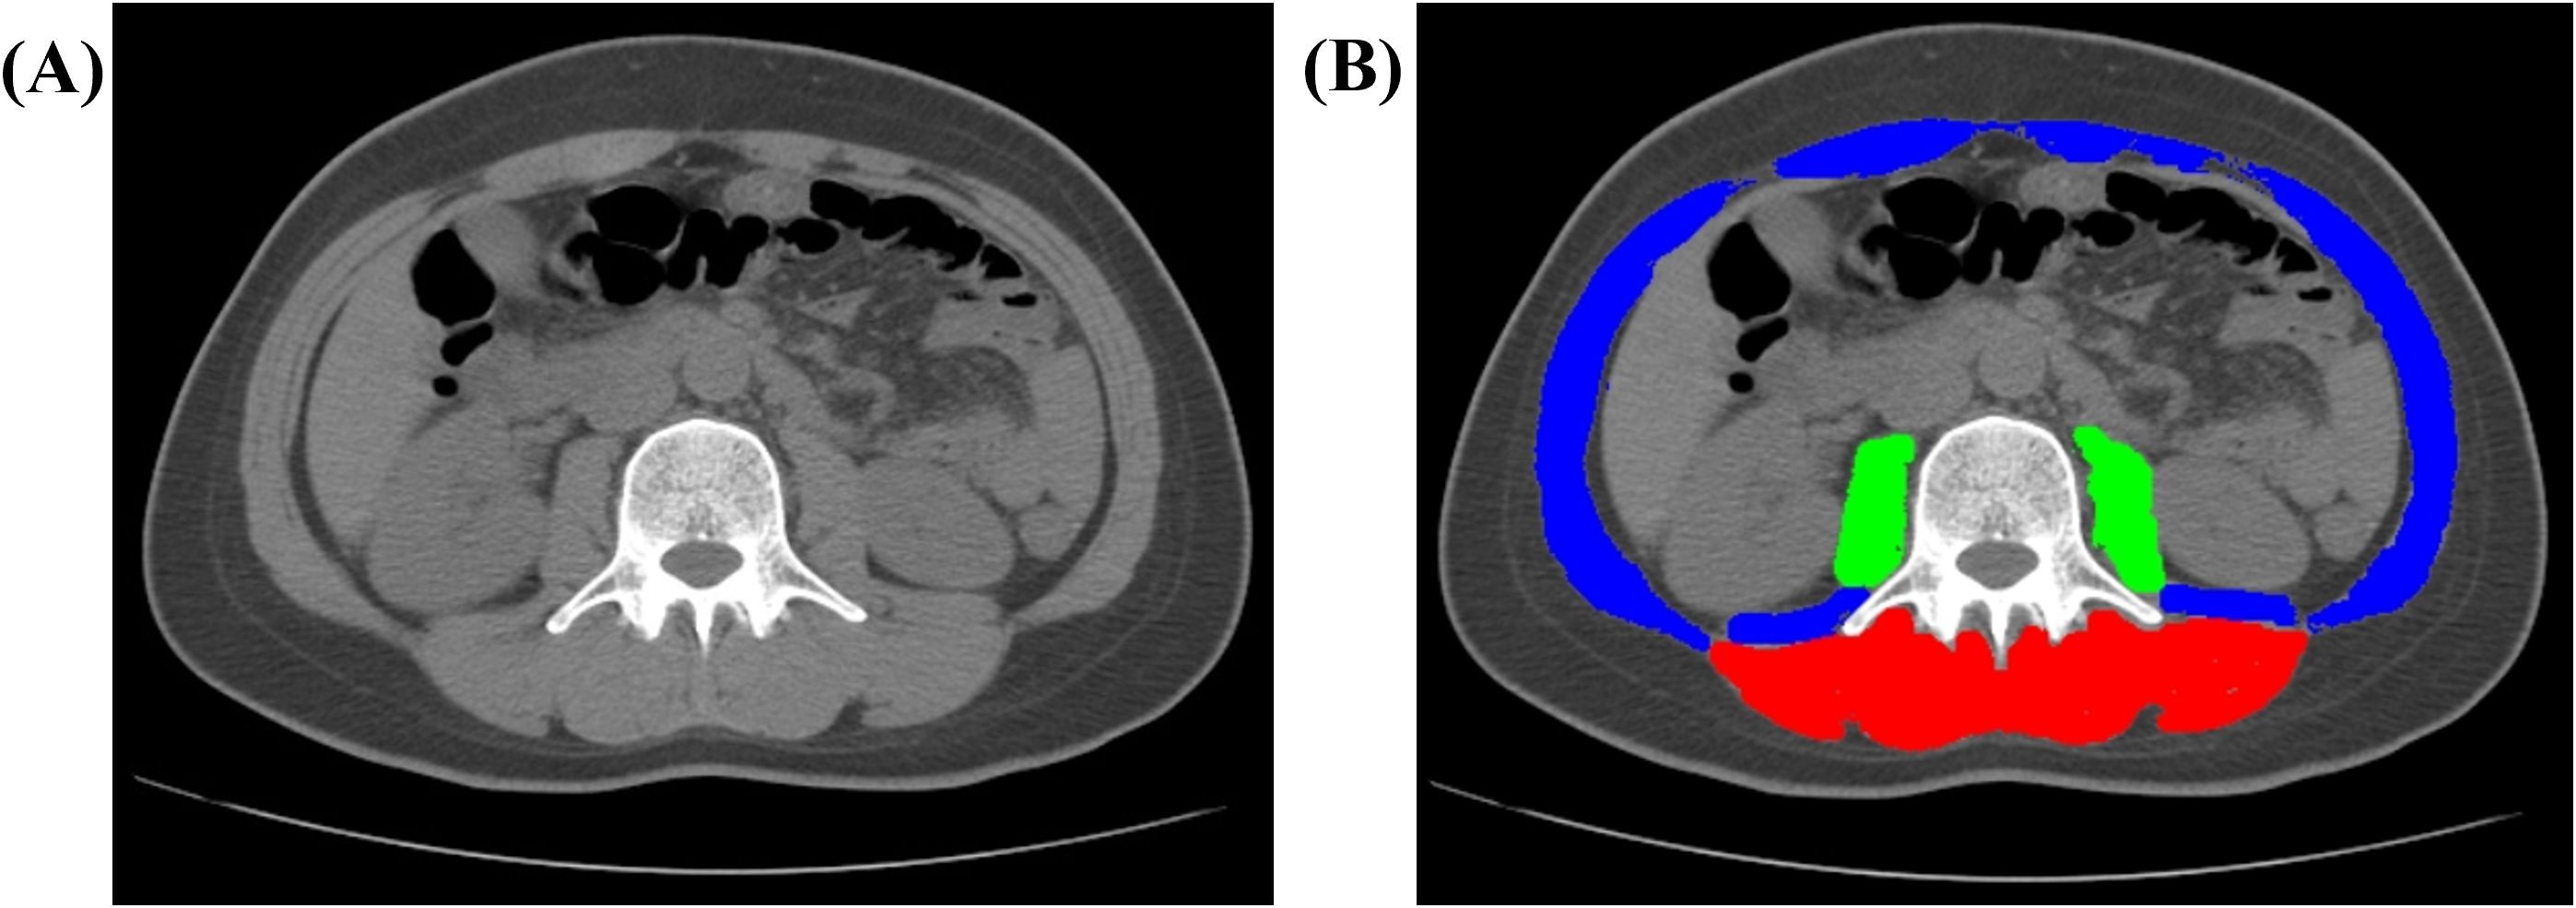

Body composition assessment and sarcopenia diagnosis

Body composition was quantified at baseline using CT axial images at the third lumbar (L3) level. SliceOmatic 5.0 (Tomovision, Canada) was used to measure cross-sectional areas (cm²) of total abdominal muscle (TAM), psoas muscle (PM), and paraspinal muscles (PS). Muscle tissue was defined using Hounsfield unit (HU) thresholds (−29 to 150 HU) (22), with manual correction for accuracy, as illustrated in Figure 1. All analyses were performed by one radiologist with 7 years of experience. Height-adjusted indices (TAM/height², PM/height²) were derived (23, 24). Sarcopenia was defined using established criteria (2325): height-adjusted TAM index <52.4 cm²/m² (men) or <38.5 cm²/m² (women); PM index <6.36 cm²/m² (men) or <3.92 cm²/m² (women); absolute PS area <31.97 cm² (men) or <28.95 cm² (women).

Figure 1. Representative CT image analysis of a 41-year-old female patient. (A) Axial non-contrast CT image acquired at the level of the third lumbar vertebra (L3). (B) Automated segmentation of muscle compartments: paraspinal muscles (PS, red), psoas major muscles (PM, green), and total abdominal muscle (TAM, combined overlay). Abbreviations: CT, computed tomography; L3, third lumbar vertebra; TAM, total abdominal muscle; PM, psoas major; PS, paraspinal muscles.